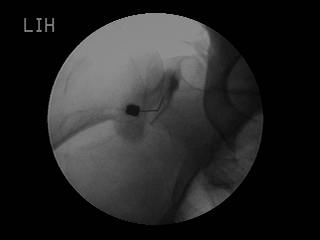

– 디스크로 인한 신경통증 치료시 (선택적 신경 차단술) 디스크가 신경에 자극을 가하면 염증증상이 발생되면서 과민반응이 발생하게 되고, 이로 인하여 허리 통증, 다리 저림등의 증상이 나타납니다. 이때 C-arm 기계를 이용하여 눌리거나 압박 받은 신경부위를 찾아 직접 병변부위에 주사하여 염증 및 부종을 가라앉혀 줍니다. 또한 유착박리제(H-lase)를 같이 주사하여 유착된 신경을 치료하게 됩니다.

– 갑작스럽게 허리를 삐끗하여 허리를 움직이기가 힘들 때 ( 내측분지 신경 차단술 ) 잘못된 자세나 행동으로 갑작스럽게 요통이 발생한 경우, 허리중심근육과 후관절이 원인인 경우가 많습니다. 이 때 C-arm 기계를 이용하여 후관절을 담당하는 신경가지를 찾아 주사로 약물을 주입해 치료하여 통증을 해소하고 염증을 가라앉힐 수 있습니다.